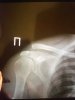

восстановление после травм с применением фармы